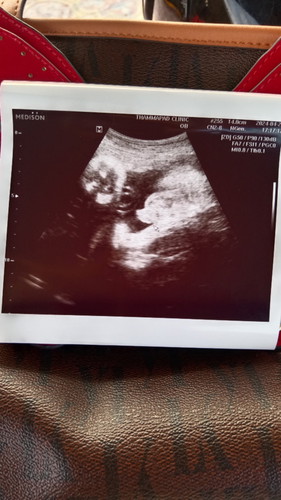

วันนี้รู้เพศแล้วค่ะ

วันนี้ไปอัลตร้าซาวด์มา ได้ลูกชายค่ะแม่ๆ